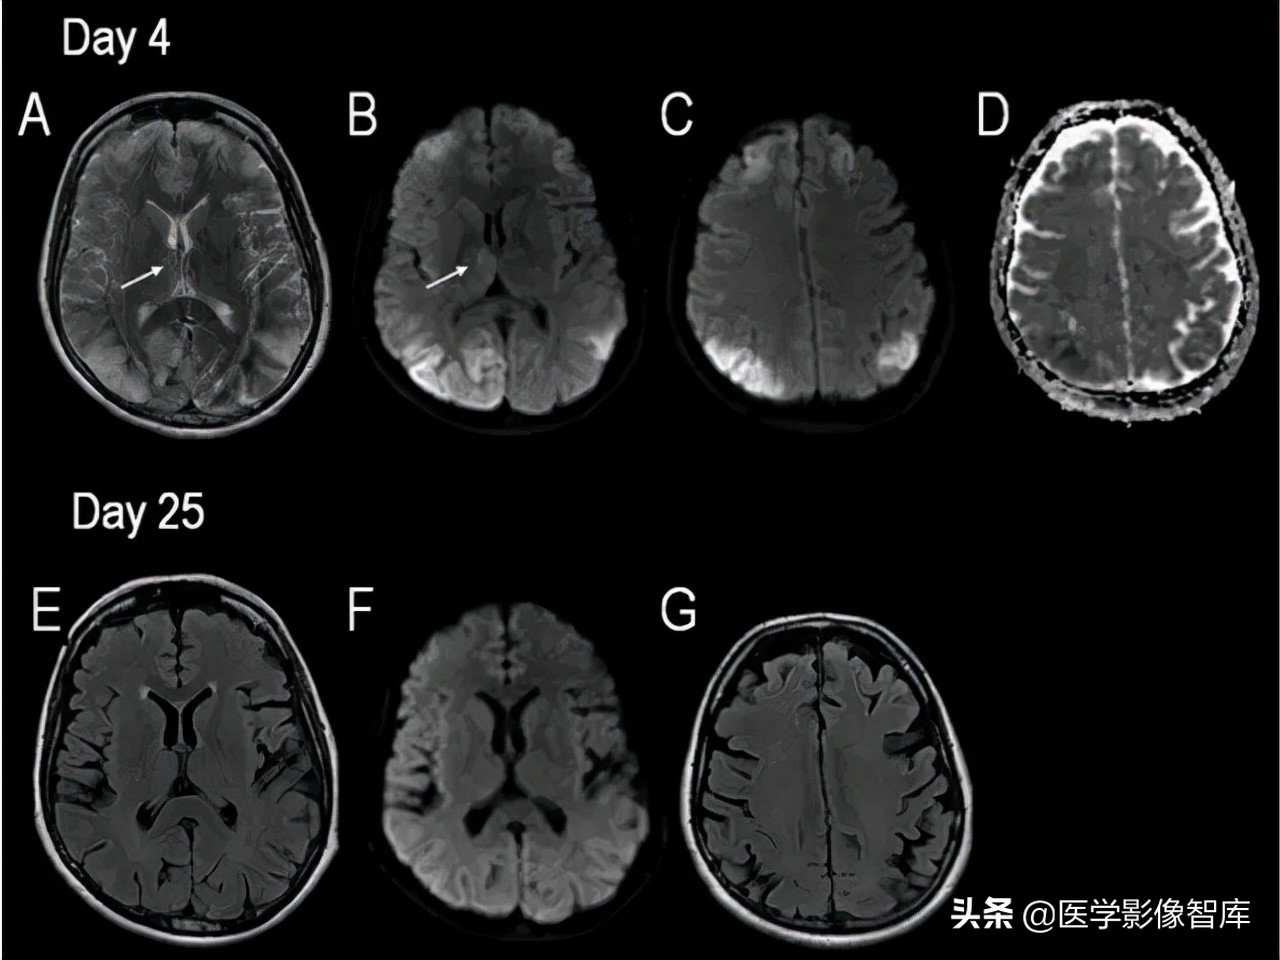

脑炎(包括病毒性脑炎、自身免疫性脑炎等)都有可能出现累及皮层 / 皮层下的 DWI 高信号。脑炎一般不难鉴别,急性起病,有发热、头痛等症状。累及皮层的脑炎会出现癫痫发作、精神症状等,行腰穿查脑脊液常规、生化、病毒抗体、自身免疫性脑炎抗体等可帮助诊断,图 1 为单疱脑炎患者发病 6 天时的磁共振检查结果。

图 1 单疱脑炎,起病 6 天,可见两侧颞叶病灶,右侧为甚,T2WI、FLAIR、DWI 均为高信号,ADC 图为低信号

对于有明确癫痫发作病史的患者,癫痫介导的脑部影像学改变需要考虑,不同于癫痫的病因(肿瘤、FCD 等),癫痫介导的脑部影像学改变往往是可逆的,磁共振上大多表现为 T2WI 高信号,约半数表现为 DWI 高信号,常见的受累部位包括皮层 / 皮层下、基底节区、白质、胼胝体、小脑,而临床上无其他特异性的表现,如图 2 所示。

图 2 42 岁女性,延长的亚临床癫痫持续状态患者所做的两次头颅 MR 结果。A 为 T2WI,B、C、F 为 DWI,D 为 ADC 图,E、G 为 FLAIR,可见发病 4 天时双侧顶枕叶可见明显 DWI 高信号病灶,T2 相也为高信号,ADC 低信号,发病 25 天时,病灶消失